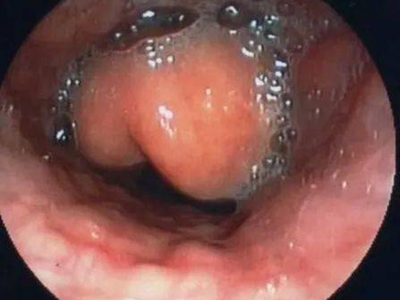

急性会厌炎是会厌及周围软组织的迅速肿胀,并可引起致命的呼吸道突然阻塞。又称为急性声门上喉炎,是会厌的急性感染,炎症发生部位以会厌为主,可向杓会厌襞以及声门上区蔓延。成人及儿童均可发病,但以成人较多见,男性多于女性,常发生于早春与秋末。

急性会厌炎起病急骤,有畏寒、发热、头痛等全身不适,多数患者体温在38-39℃。以剧烈的咽喉疼痛为主要症状,吞咽时加剧,重者饮水呛咳、流涎。喉镜下可见会厌舌面黏膜充血,高度肿胀水肿呈圆球状如卷曲香肠,肿胀可偏于一侧,偶见有黏膜溃疡。